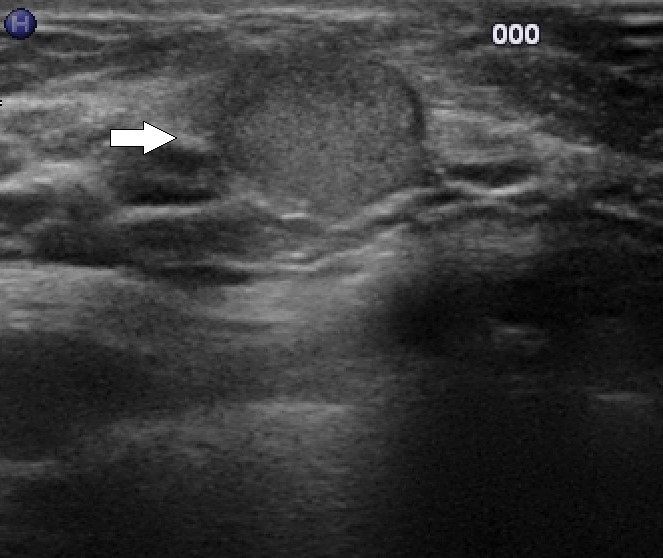

Ein Fibroadenom ist eine gutartige Geschwulst, die aus Drüsen- und Bindegewebe besteht und in der Brustdrüse vorkommt. Es ist die häufigste gutartige Brusttumorerkrankung bei Frauen im gebärfähigen Alter. Ein Fibroadenom in der Mammasonographie zeigt sich typischerweise als eine ovale oder runde, glatt begrenzte, homogene und echoarme Läsion. Die Läsion ist meist gut verschieblich. Die Mammasonographie kann helfen, ein Fibroadenom von anderen Brustveränderungen zu unterscheiden und die weitere Behandlung zu planen